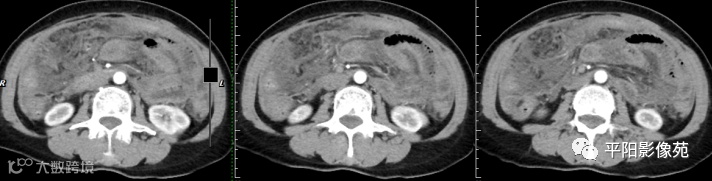

腹部增强 延迟期

壁腹膜增厚伴或不伴腹水;增厚的腹膜光滑、均匀,呈线带状,部分可见腹膜结节,网膜及肠系膜广泛浸润性改变;增强扫描明显强化。

合并淋巴结肿大,可钙化,若中心干酪样坏死,增强扫描环形强化

干型:干酪性肠系膜淋巴结病、纤维粘连、增厚,网膜饼状改变

纤维型:网膜饼状团块